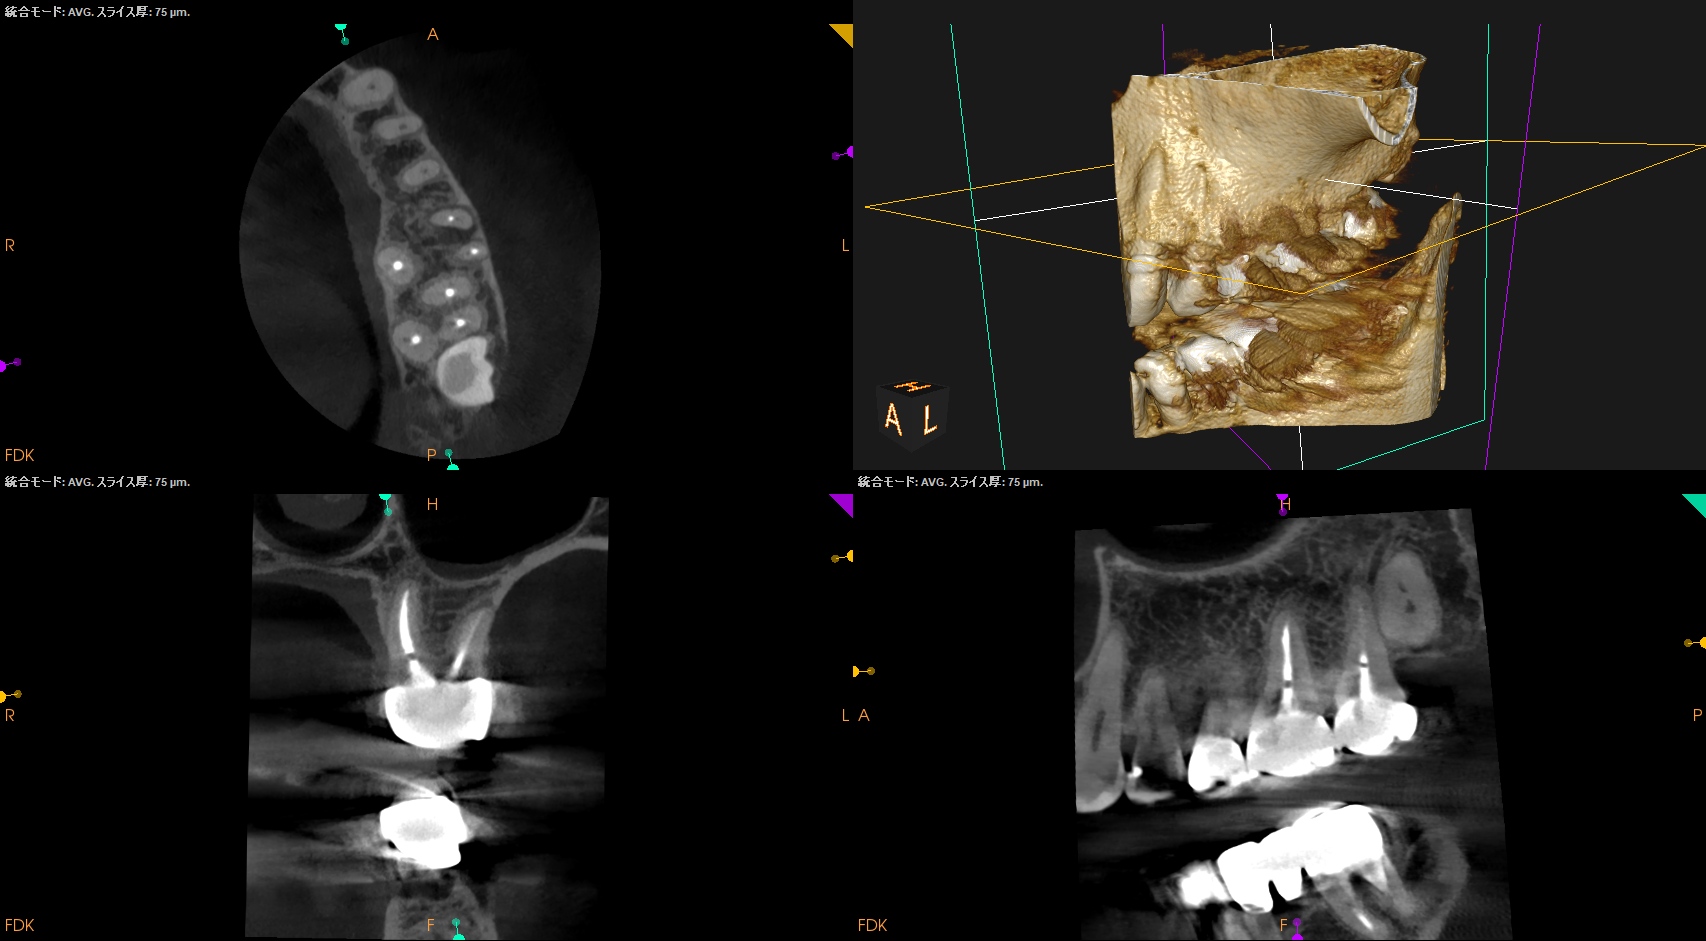

#14 Post-op 1yr recall(2026.3.27)

PA, CBCTを撮影した。

MB

DB

P

外科時と比較した。

問題は劇的に解消した。

ということでこの日で終診とさせていただいた。